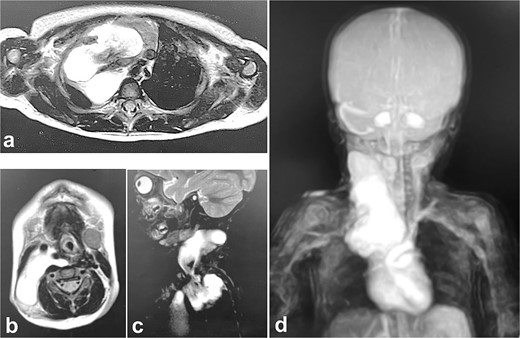

Intra- and post-operative findings from the first operation. (a) Intraoperative findings showed a huge bulge in the right neck. (b) A Denver shunt (peritoneovenous shunt) was inserted from the right cervical region to the abdominal cavity for volume reduction of the cervical cyst to prevent airway obstruction. Pump chamber with backflow prevention valve was implanted in the right anterior chest subcutaneous tissue. (c) Post-operative findings showed a reduction in the right neck swelling, even when crying. (d) The pressure on the trachea was shown to be relieved on the X-ray.